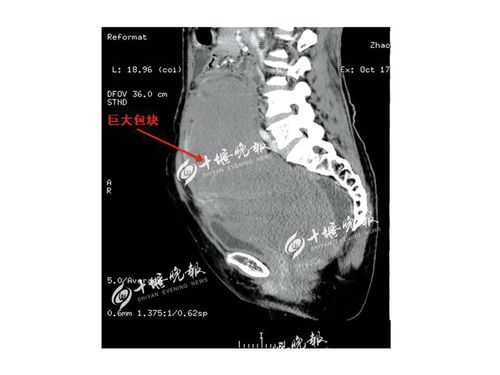

直径31厘米,如篮球般大小,在腹腔内犹如孕育了几个月的胎儿,你见过